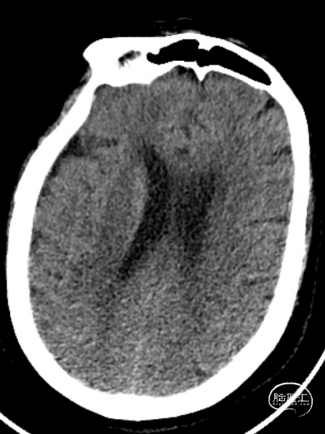

术前检查

患者为急性脑梗死,头颅CT未见明显低密度病灶,CTA提示:右侧颈内动脉及右侧大脑中动脉M1段闭塞,远端分支减少,显影浅淡。目前患者神经功能缺损严重,有急诊取栓手术指征。

术后第一天复查颅脑CT未见异常染色及大面低密度病灶。

查头颅MRI:右侧基底节区、右侧顶颞岛叶急性脑梗死。